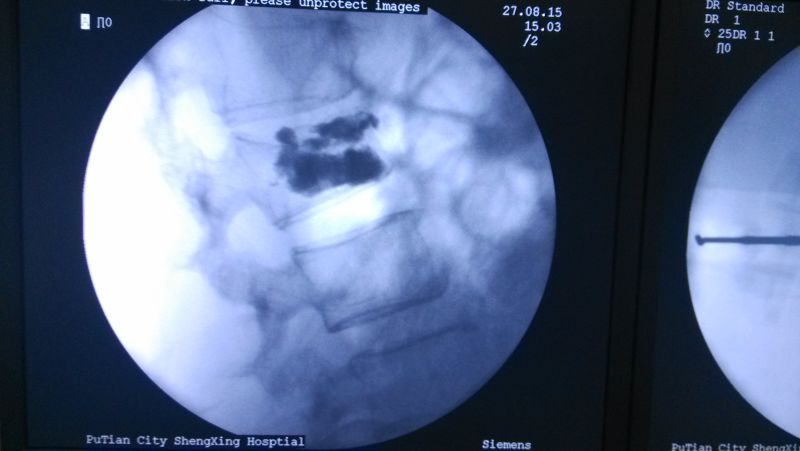

術(shù)中透視

注射骨水泥

中醫(yī)科曹平主任組織全科醫(yī)生,對林阿婆的病情進行討論、分析。認(rèn)為該病人可以采取“椎體成形術(shù)”進行治療,精心制定了手術(shù)方案。8月27日,林阿婆被送入手術(shù)室,在林伯龍主治醫(yī)師的操作下,通過C型臂X光機透視定位,成功完成穿刺,并順利注入骨水泥。